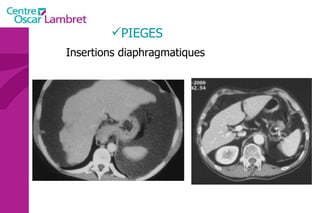

PIEGES Insertions diaphragmatiques